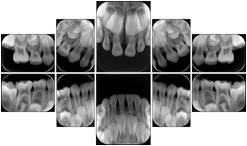

Intra-oral radiography typically involves acquisition of multiple images of various parts of the dentition. Many digital radiographic systems offer customized templates that are used for displaying the images in a study on the screen. These templates may also be referred to as mounts or view sets. The Structured Display Object represents a standard method of encoding and exchanging the layout and intended display of Structured Displays. A structured display object created in this manner could be stored with a study and exchanged with images to allow for complete reproduction of the original exam.

In most standard cases, images are oriented in structured layouts. These structured displays are useful to be shared between providers for reference purposes.

Table OO.1.1-1 shows structured display standard templates, where Viewset ID is based on the Japanese Society for Oral and Maxillofacial Radiology (JSOMR) classification provided by JIRA (Japan Medical Imaging and Radiological Systems Industries Association, www.jira-net.or.jp). Expected or typical teeth to be imaged location, region and designation codes are based on ISO 3950-2010, Dentistry - Designation system for teeth and areas of the oral cavity. For all the hanging protocols listed in OO.1.1-1, the value to use for Hanging Protocol Creator (0072,0008) is "JSOMR" and the value to use for Hanging Protocol Name (0072,0002) does not include "JSOMR" (e.g., "DL-S001A", not "JSOMR DL-S001A").